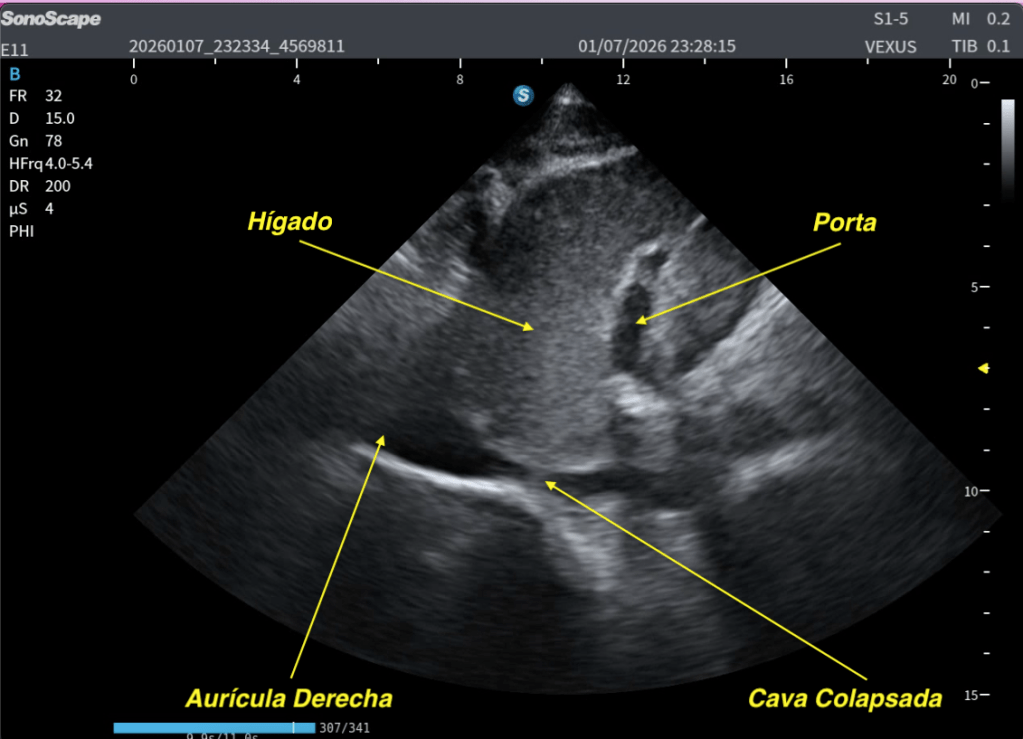

Esta maniobra demuestra, en este caso, normalidad.

Te lo explico en las dos siguientes imágenes:

✅Normalidad de la Cava con el SNIF.

El colapso de la VCI durante el sniff es una respuesta fisiológica normal que indica que el corazón derecho puede reducir la presión auricular derecha y adaptarse al aumento del retorno venoso.